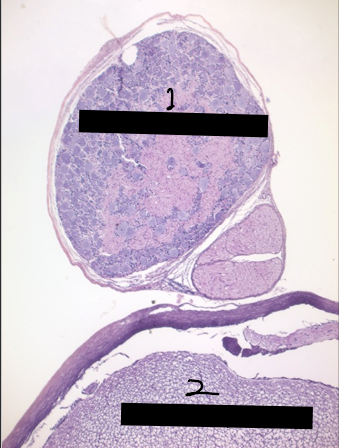

3

afferent neuron cell bodies

4

nucleus

5

nucleolus